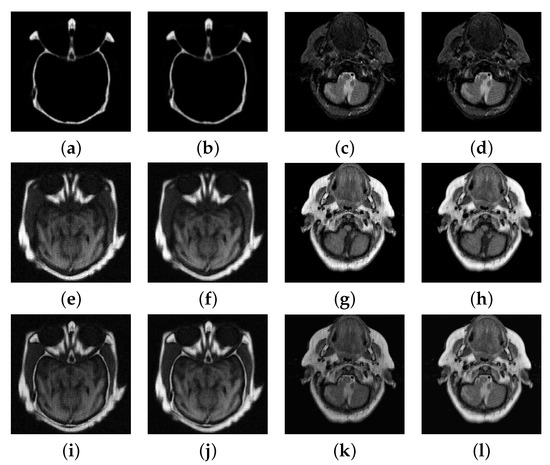

4.3. Numerical Experimental Results and Analysis

| Method | Index | CT/MRI | MR-T1/MR-T2 | Multifocus1 | Multifocus2 |

|---|---|---|---|---|---|

| proposed | 2.51 | 3.11 | 4.32 | 4.69 | |

| 0.59 | 0.39 | 0.39 | 0.54 | ||

| 0.44 | 0.37 | 0.48 | 0.69 | ||

| DDTF | 2.63 | 2.72 | 3.49 | 3.54 | |

| 0.46 | 0.40 | 0.37 | 0.47 | ||

| 0.33 | 0.28 | 0.25 | 0.46 |